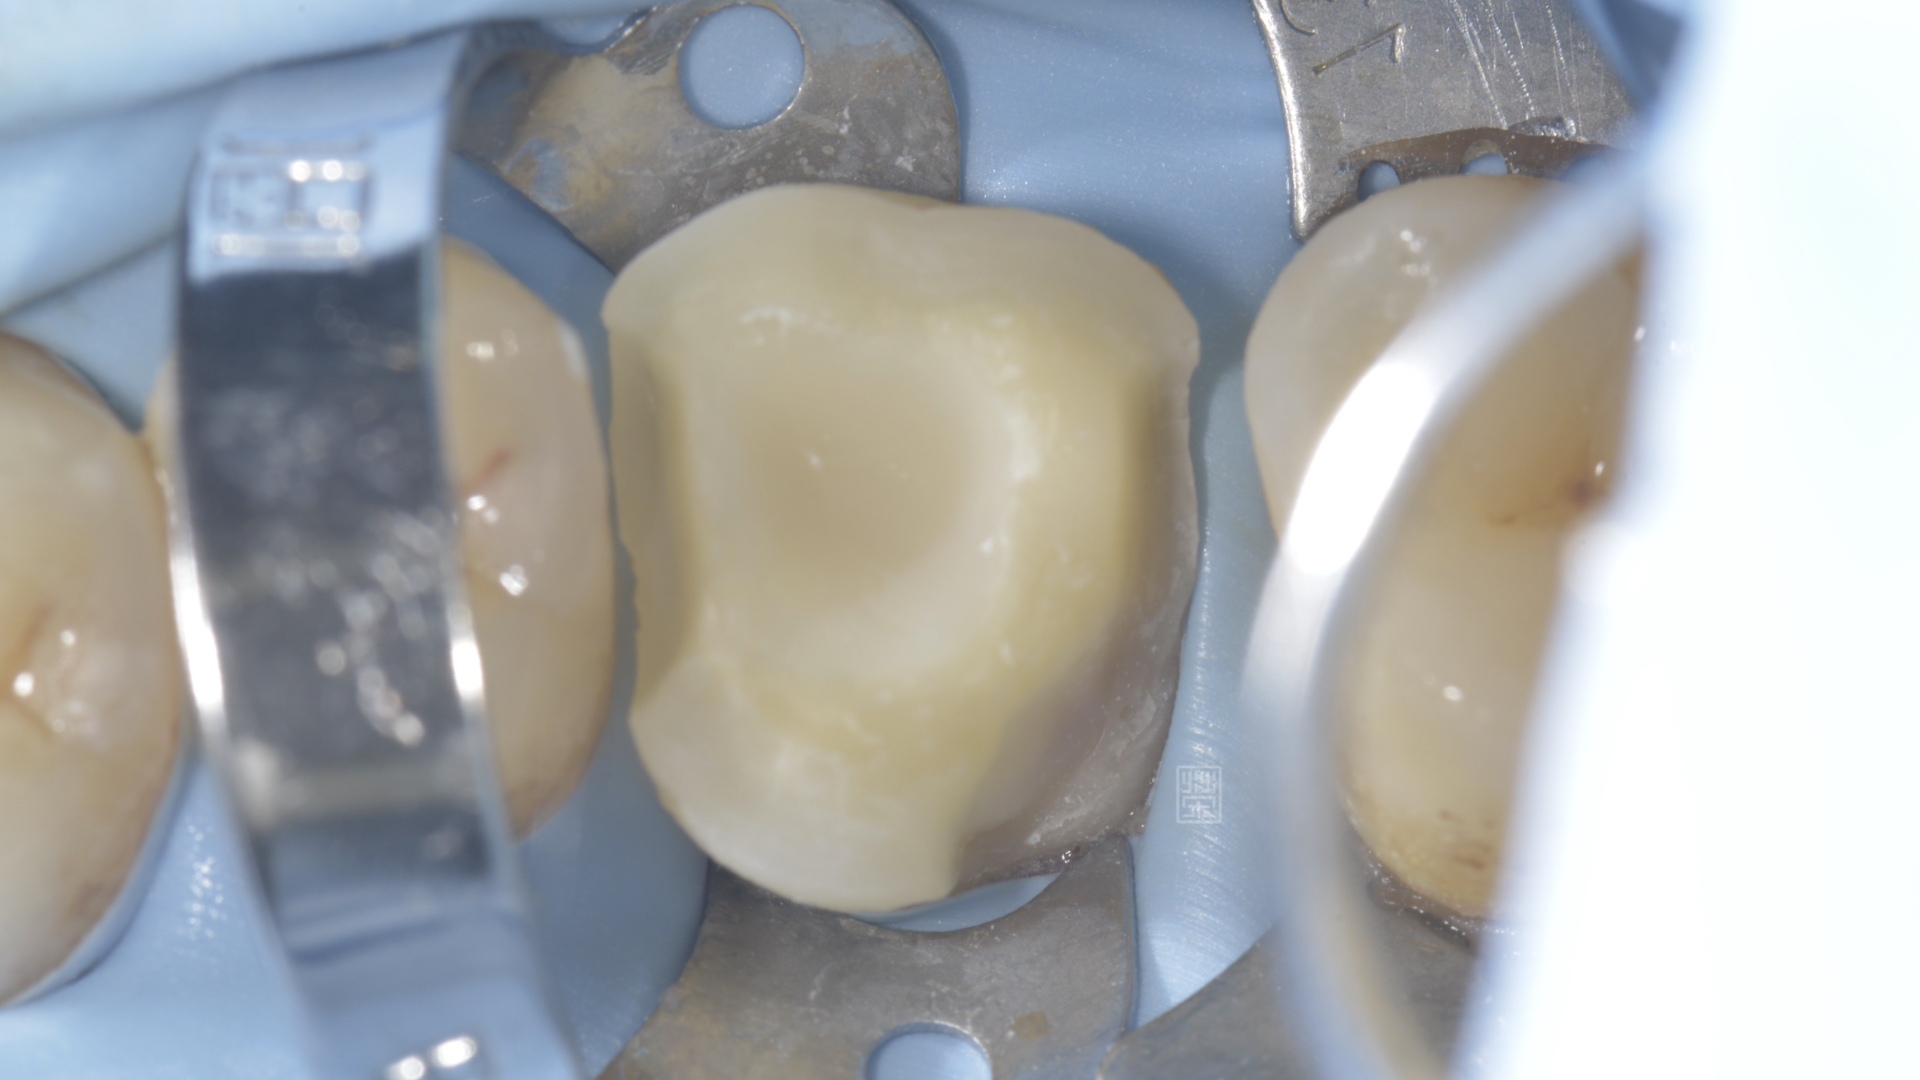

牙冠增長術將邊緣裸露出,以利全瓷嵌體邊緣製作

根管治療後,將邊緣修順,給全瓷嵌體走夠的空間

全瓷嵌體完成